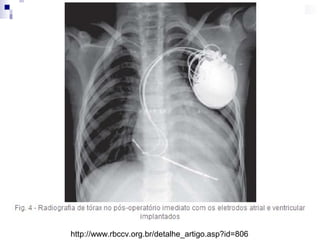

Características do procedimento de

implante

http://www.rbccv.org.br/detalhe_artigo.asp?id=806